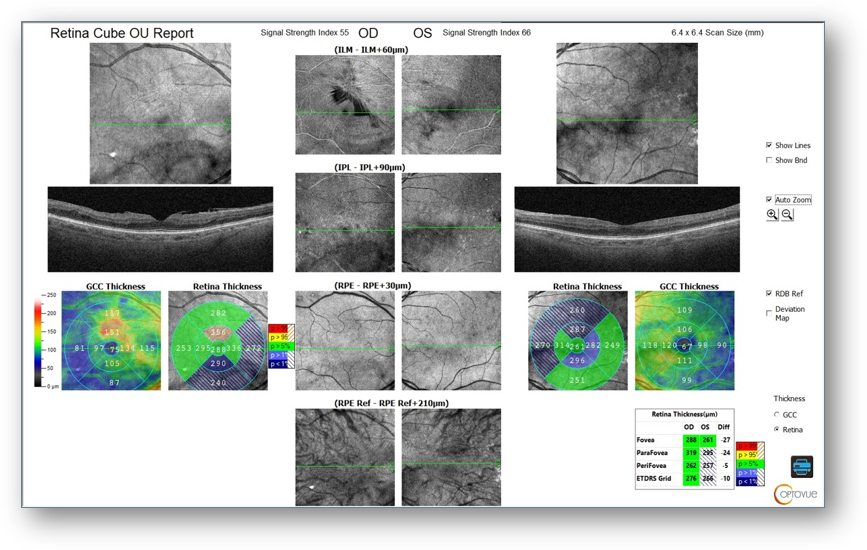

There was also evidence of ongoing vascular changes on OCT-A, including an irregular/asymmetric foveal avascular zone and capillary dropout (Figure 2) along with moderate ERM OD with central microaneurysms on OCT (Figure 3). As such, I wanted to monitor for progression that might require additional intervention.

Figure 2: OCT-A

Figure 3: OCT